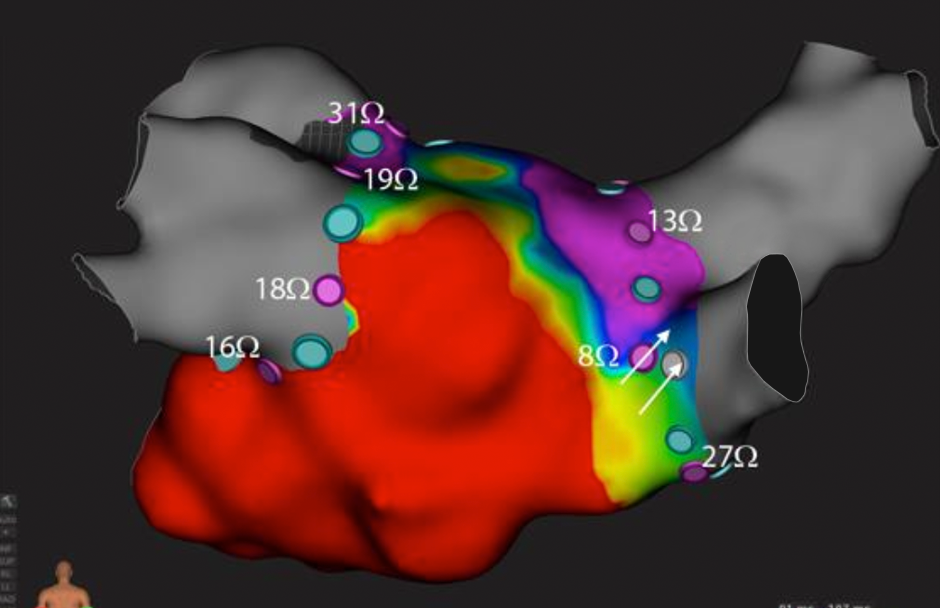

Pre-ablation Local Impedance is Predictive of Lesion Formation in Patients with Paroxysmal Atrial Fibrillation: Results of the LOCALIZE Clinical Trial

HRS 2020 Science Online, Das, et al., May 2020

Local Impedance Drop During Pulmonary Vein Isolation Predicts Late Reconnection in Patients with Paroxysmal Atrial Fibrillation: Results of the LOCALIZE Clinical Trial (Download Abstract)

HRS 2020 Science Online, García-Bolao, et al., May 2020. Distributed with permission from the Heart Rhythm Society.